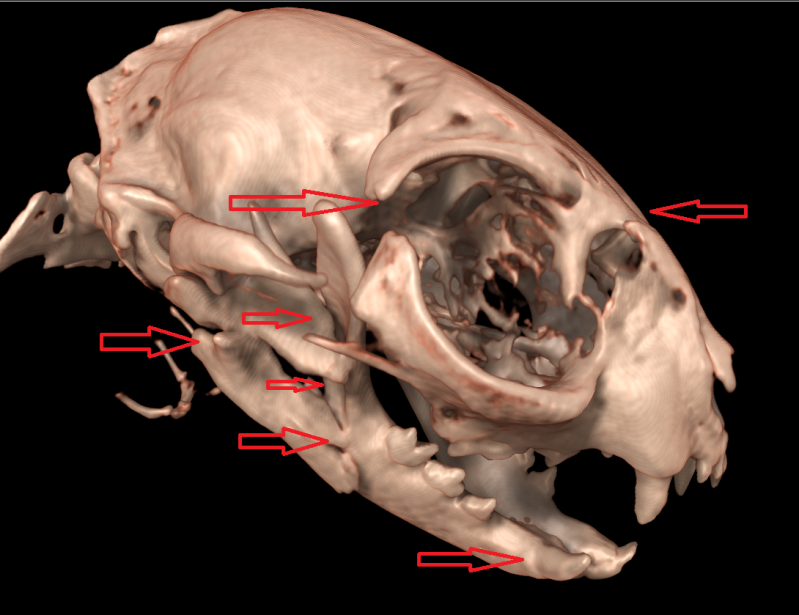

3D beeld van kop van kat met 9 breuken